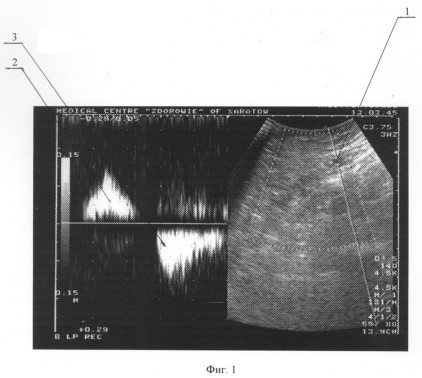

Пациент Б., 52 лет. При физикальном осмотре выявлено варикозное расширение большой подкожной вены и ее притоков на правой нижней конечности, положительный симптом Гаккенбруха на уровне правого сафено-феморального соустья. При дооперационном ультразвуковом дуплексном ангиосканировании в вертикальном положении выявлен патологический сафено-феморальный рефлюкс справа, в горизонтальном положении патологических венозных сбросов выявлено не было. Окончательный диагноз: Варикозная болезнь нижних конечностей. Частичная клапанная недостаточность большой подкожной вены справа. На фиг.1 и 2 представлены результаты ультразвукового дуплексного ангиосканирования большой подкожной вены в верхней трети бедра в ортостазе; на фиг.1 – во время проведения дистальной компрессионной пробы, на фиг.2 – во время выполнения пробы Вальсальвы, где 1 – просвет большой подкожной вены, 2 – антеградный кровоток по большой подкожной вене при компрессии икроножных мышц, 3 – ретроградный кровоток по большой подкожной вене при декомпрессии икроножных мышц, 4 – ретроградный кровоток по большой подкожной вене при выполнении пробы Вальсальвы.